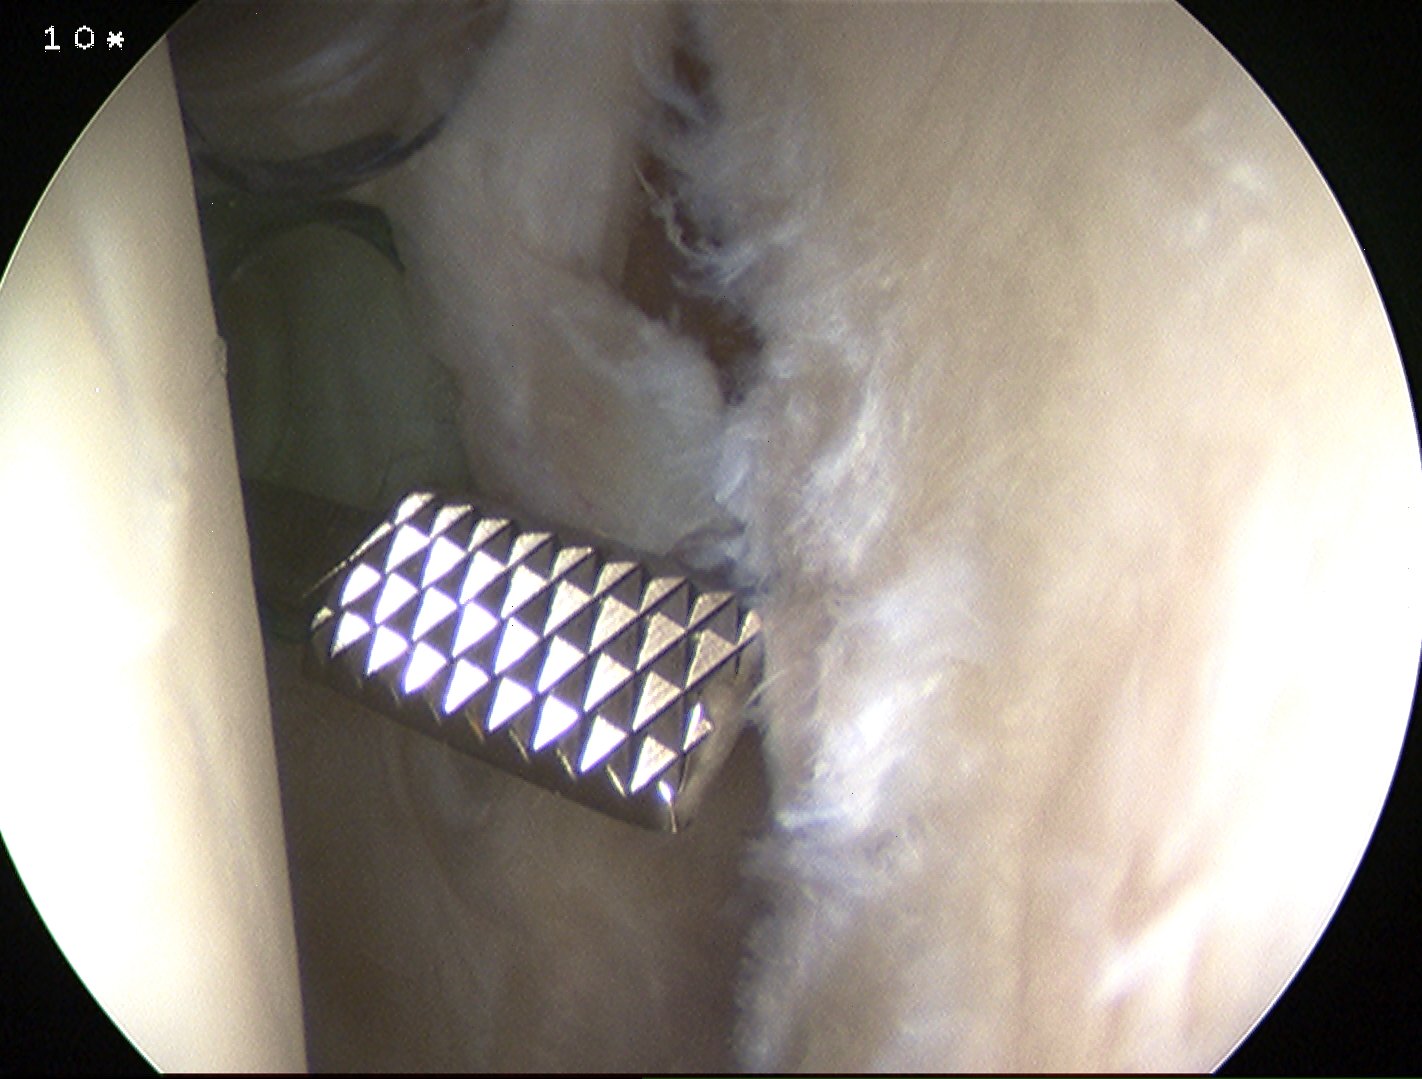

Insert anchors

Inferior anchor at 5.30 o'clock

- curved anchor guide / trans-subscapularis

- on rim of glenoid

Other anchors typically at 3 and 4 o'clock

Arthroscopy Bankart Anchor Drill GuideInferior Glenoid Anchor